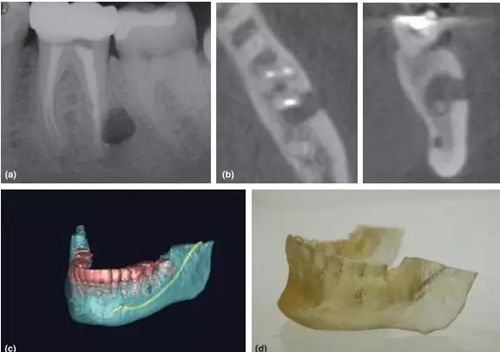

3,根尖周手術(shù)的術(shù)前評(píng)估

CBCT一直被倡導(dǎo)用于評(píng)估和設(shè)計(jì)根尖周手術(shù)方案 (Rigolone et al. 2003; Tsurumachi & Honda 2007; Kim & Kratchman 2006)。三維重建圖像讓臨床醫(yī)生能判斷根尖與鄰近重要解剖結(jié)構(gòu)的關(guān)系,如下頜神經(jīng)管、髁孔和上頜竇等。除外,還能精準(zhǔn)測(cè)量骨損實(shí)際大小、與牙根的關(guān)系、皮質(zhì)骨板厚度、骨開窗情況和牙根的傾斜角度(Nakata et al. 2006)。

CBCT掃描還能配合3D打印技術(shù),把掃描的術(shù)區(qū)立體重建并打印出來,得出真實(shí)比例的研究模型,有助于術(shù)者對(duì)手術(shù)方案的設(shè)計(jì)和過程的演練(Scarfe et la. 2006)。